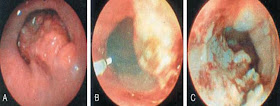

Endoskopik Muayene: Özofagus karsinomundan şüphelenilen tüm hastalarda endoskopik muayene yapılmalıdır. Endoskopik muayene bunların dışında radyolojik olarak anormal bulunan lezyonları teyit etmek ve bu lezyonlardan biyopsi almak gayesi ile de yapılır.

Özefagus kanserinin lazer tedavisi

Stend Uygulanması